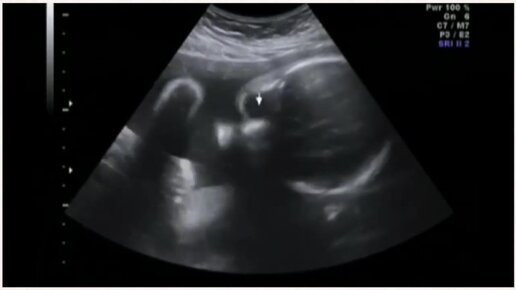

УЗИ на 29 неделе беременности